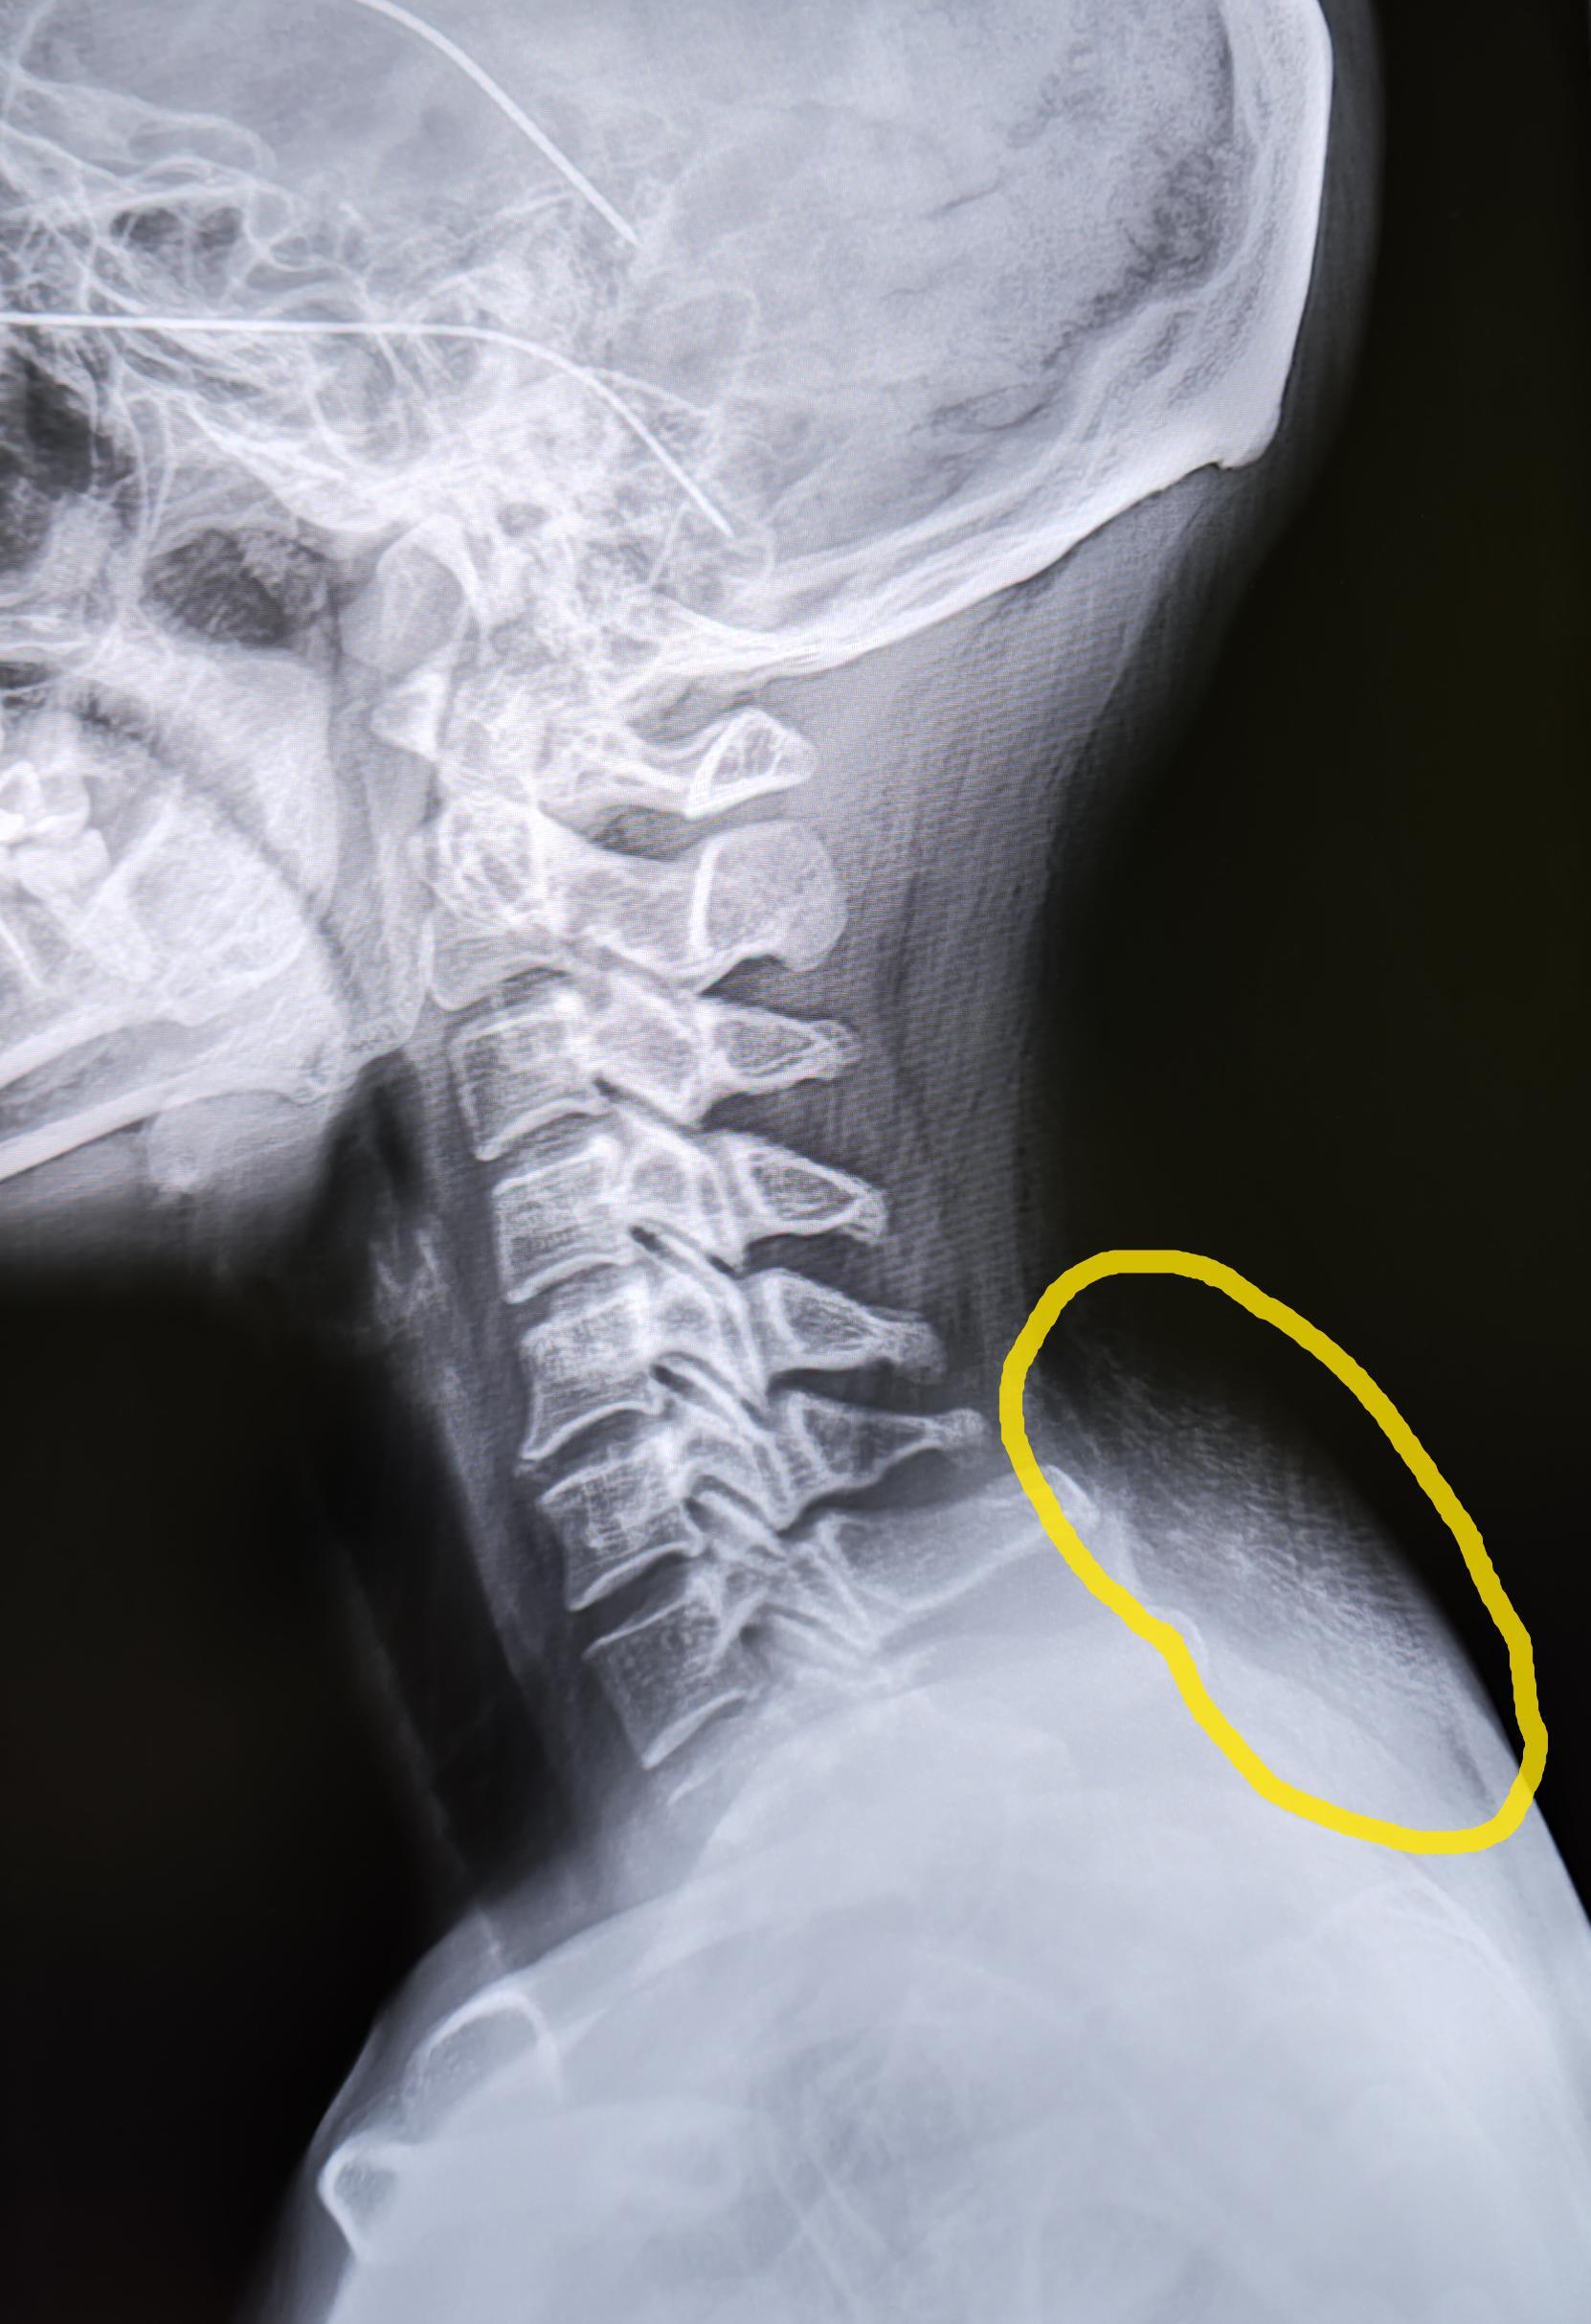

Вдовий горб(локальная липодистрофия)

Пациентка (34года) пришла на Р-гр. ШОП, с жалобами на возникшее образование по задней поверхности шеи.

Вдовий горб – локальное скопление жировой ткани на границе шеи и спины при котором образуется характерная выпуклость.